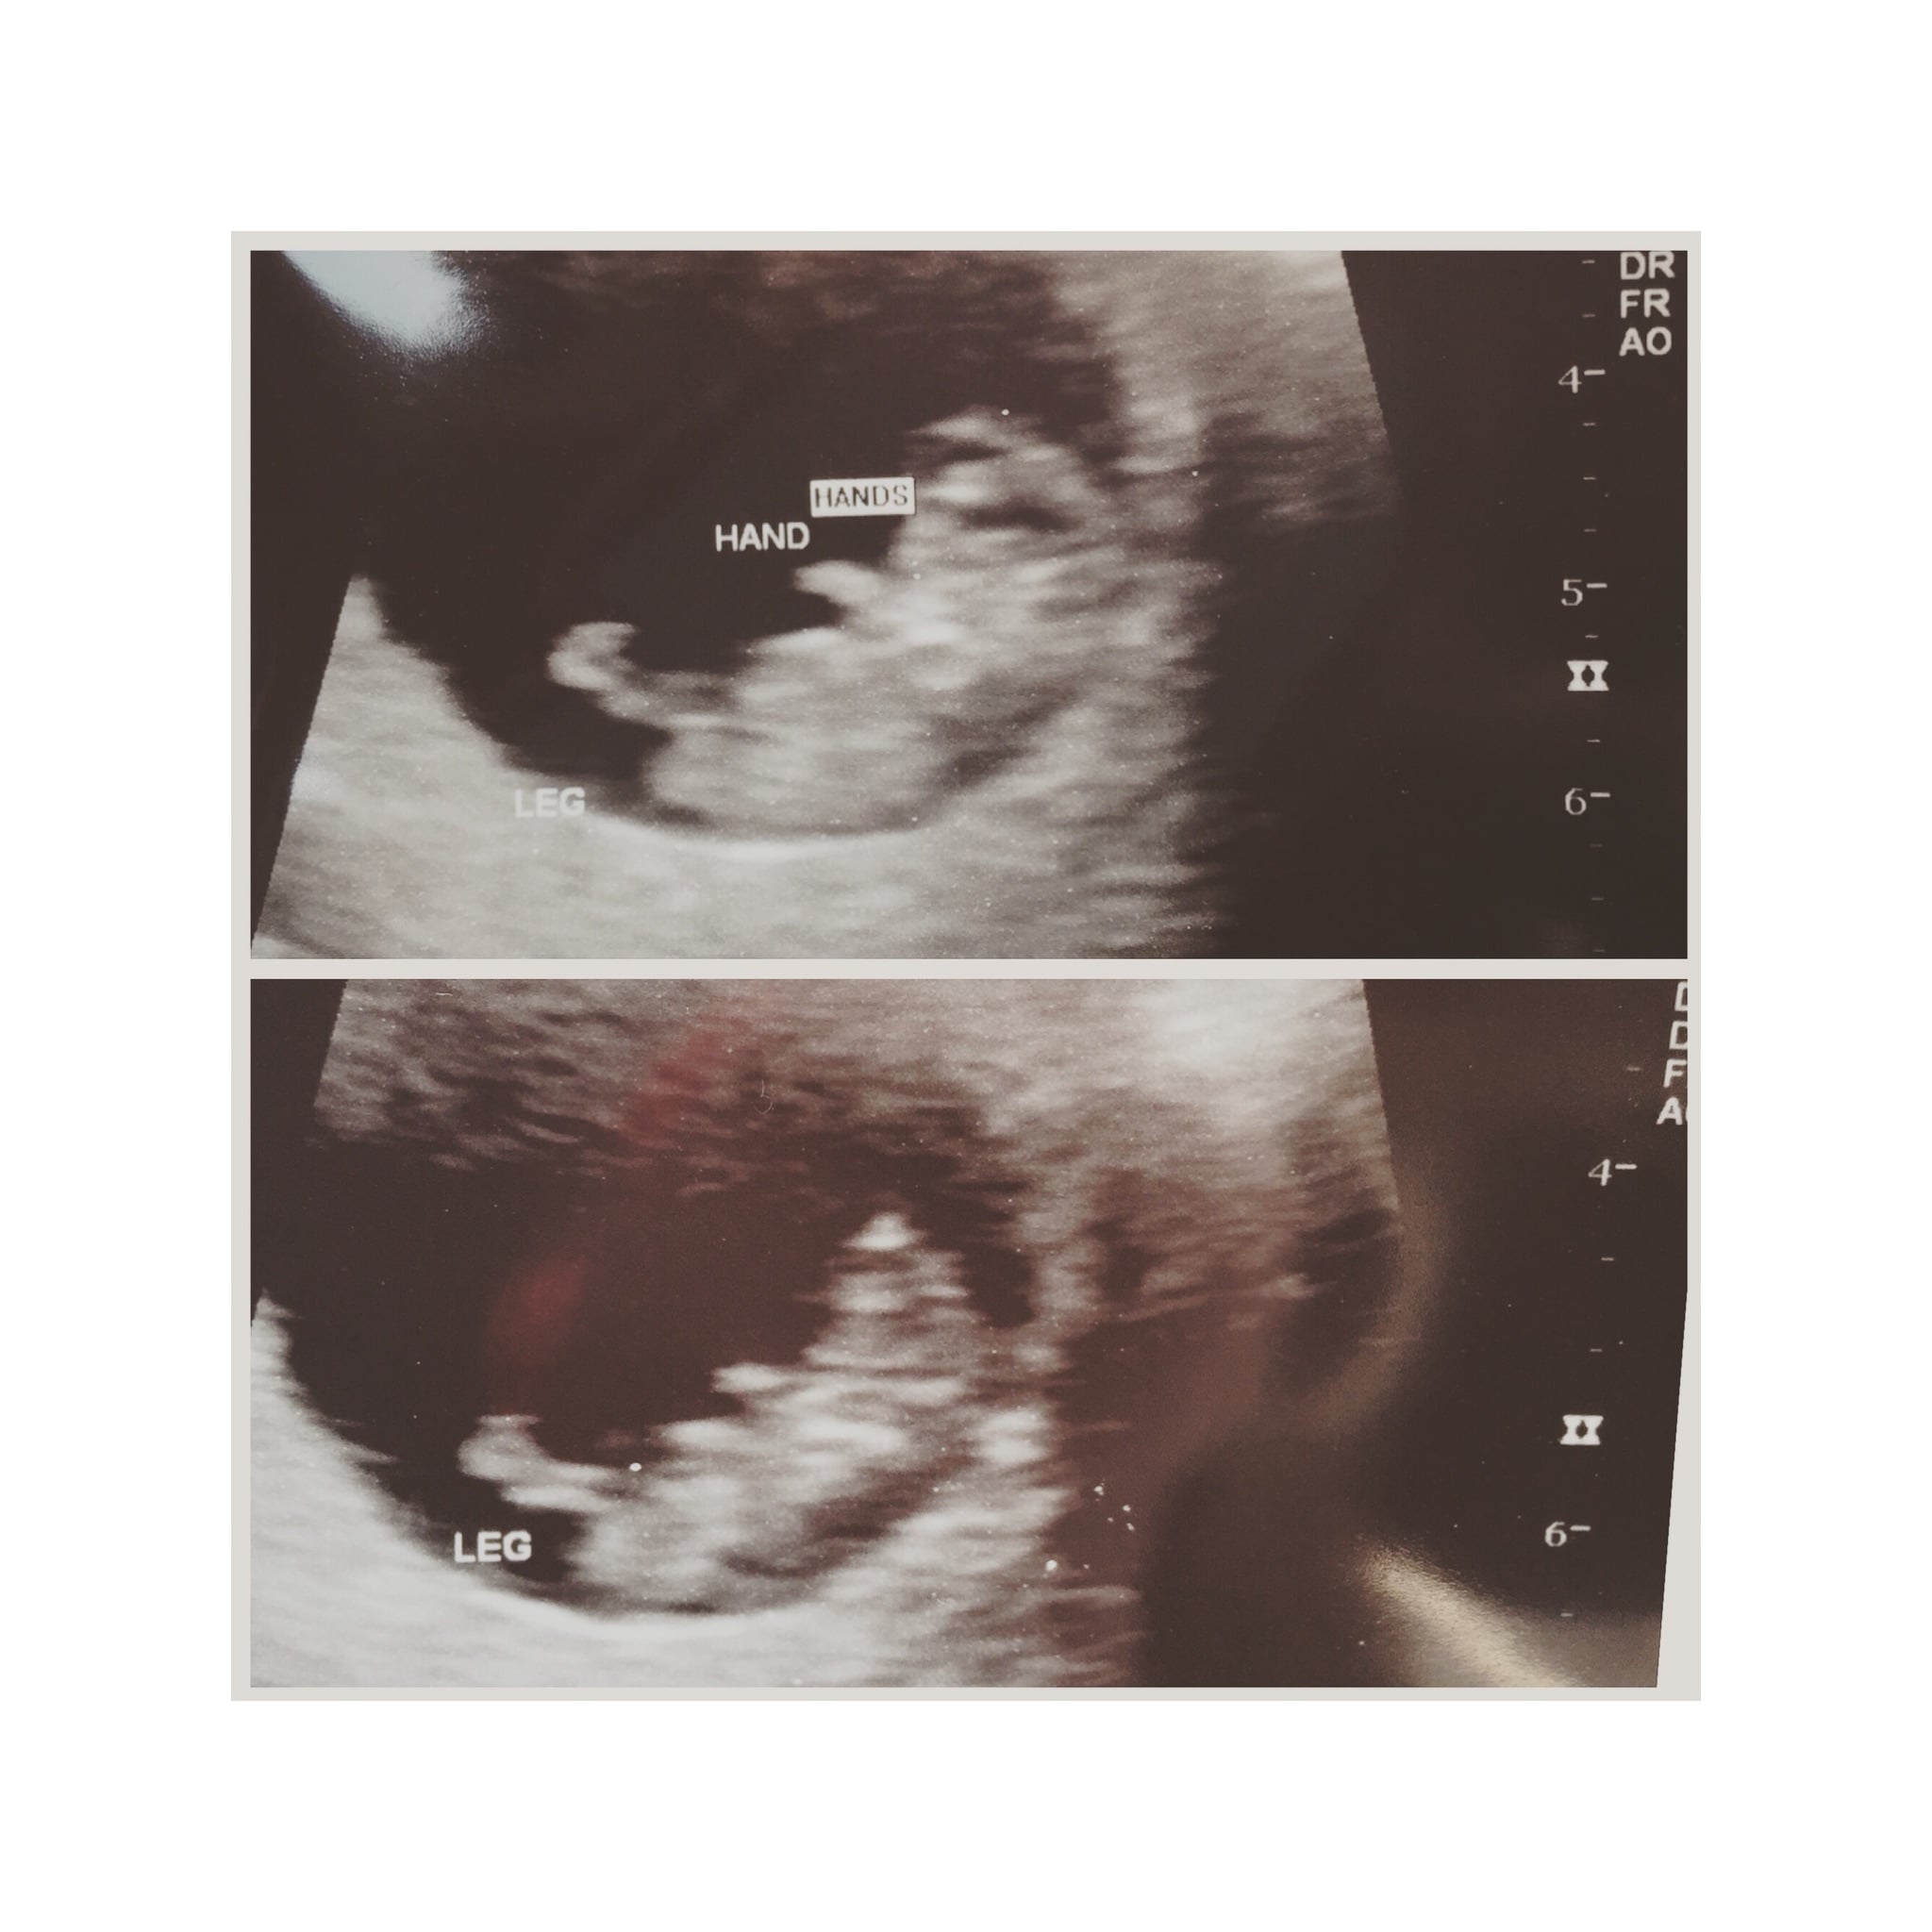

I already knew we were having a boy from the MaterniT21 blood test but we could clearly see the penis on today's ultrasound (12 weeks 3 days).

I'm high risk and have quick ultrasounds with every OB visit.

Anyway, the point of my post is that if any of you have a 12 week ultrasound coming up, and it's a boy, you may be able to see!

(Obviously quality of US machine, baby's position, uterine positioning, etc all come into play.)